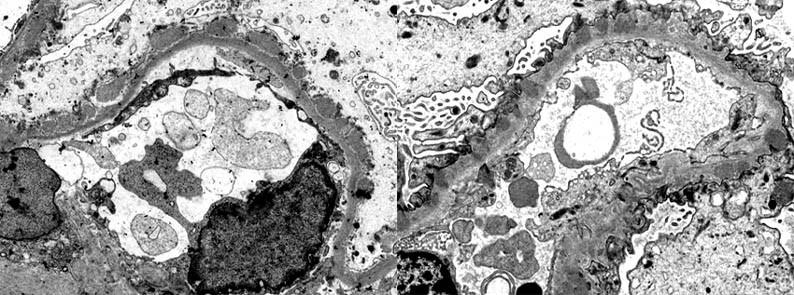

A 7-year-old boy presents with facial oedema, dark urine, and decreased urine output one week after recovering from a sore throat. His blood pressure is 140/90 mmHg. Laboratory investigations reveal elevated creatinine, haematuria, and low serum C3 complement level. A renal biopsy is performed.

Based on the clinical history, laboratory findings, and light microscopic appearance of the renal biopsy, which of the following is the most likely diagnosis?

A. IgA nephropathy

B. Anti-GBM disease

C. Post-infectious glomerulonephritis

D. Pauci-immune ANCA-associated glomerulonephritis

E. Minimal change disease

Q4 Explained

■ Correct Answer (C): Post-infectious glomerulonephritis (PIGN) is the MOST likely diagnosis. The clinical history of recent infection, acute nephritic syndrome, low C3 complement, and diffuse endocapillary proliferation are all consistent with this diagnosis.

■ Incorrect Answer (A): IgA nephropathy typically presents with recurrent macroscopic hematuria often coinciding with or following an upper respiratory tract infection, and usually has normal C3 levels. While it can occur in children, the history is less typical. The histology will also typically show mesangial proliferation.

■ Incorrect Answer (B): Anti-GBM disease typically presents with rapidly progressive glomerulonephritis (RPGN) with crescent formation on the renal biopsy, and linear IgG deposition on IF, neither of which are described in the scenario.

■ Incorrect Answer (D): Pauci-immune ANCA-associated GN typically presents as a rapidly progressive glomerulonephritis (RPGN), often with systemic features, including constitutional symptoms, arthralgia, weight loss and is less common in children. A preceding infection is unusual.

■ Incorrect Answer (E): Minimal change disease presents with nephrotic syndrome and normal appearing glomeruli on light microscopy. The renal function is also typically normal.